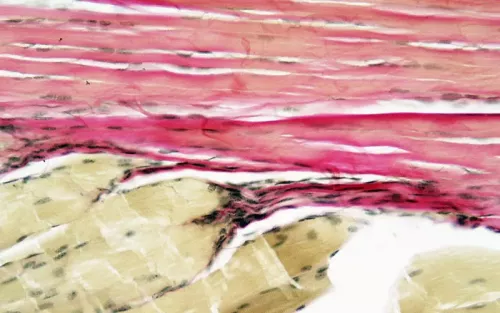

One of these built-in systems for moving with refinement, relaxation, and efficiency is the Golgi-based stretch reflexes. Golgi mechanoreceptors are common in many of the body's dense connective tissues, such as joint capsules, ligaments (where they are known as Golgi end organs), and Golgi tendon organs (GTOs), which are concentrated around the myotendinous junctions, where muscle cells end and tendons begin (Image 1).1 Intimately involved in tension perception, protective reflexes, and movement coordination, with the right kinds of mechanical stimuli, GTOs can lower the firing rate (i.e., relax) of their associated muscles (Image 2). Interestingly, they can also facilitate (increase the firing rate, or excite) a muscle's synergists and antagonists, and thereby play a key role in de-emphasizing prime-mover dominance and increasing global movement coordination and refinement.2